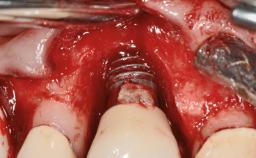

Biological complications caused by undetected cement residue have been receiving much attention. Excess cement might be responsible not only for rapidly developing of peri-implantitis, but also for delayed or chronic manifestations of the disease many years after cementation (Wilson 2009; Linkevicius and coworkers 2013). Invitro and clinical studies have shown that it is very difficult or even impossible to completely clean up excess cement at subgingival margins, so popular in cemented restorations (Agar and coworkers 1997; Linkevicius and coworkers 2011, 2012). Possible outcomes of biological complications due to excess cement range from temporary inflammation of the peri-implant soft tissues without any serious esthetic and functional consequences all the way to implant loss. This report describes a case of peri-implantitis caused by residual cement; as well as the management and quite unusual resolution of the complication. The patient presented in 2009 with a draining sinus tract, tenderness on chewing, and tissue contact above the implant-supported restoration. The implant had been restored approximately three years before.